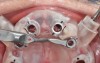

Fig 14. Printed static guide used to precisely control preparation of osteotomy (Fig 14) and delivery of the implant through the guide (Fig 15).

Figure 14

Fig 15. Printed static guide used to precisely control preparation of osteotomy (Fig 14) and delivery of the implant through the guide (Fig 15).

Figure 15

From the data and collaboration in steps 1 through 3, surgical guides can be fabricated for static surgery, and when indicated, prosthetic components, such as custom healing abutments, provisional crowns, or fixed partial dentures, can be produced for delivery at the time of surgery to guide soft-tissue healing. The static approach, better known as computer-guided surgery, refers to the use of tissue-tooth or soft- and hard-tissue-supported surgical templates. In essence, the virtual implant position planned from the CBCT, IOS, and face-in data sets is reproduced. The guide is produced with master cylinders (portals) through which the osteotomy preparation drills are introduced, and in full-guidance cases, the delivery of the implant is carried out (Figure 14 and Figure 15). Dynamic guided surgery or computer "navigation" traces the virtual implant position directly from CBCT data and employs motion tracking or real-time tracking technology to prepare the implant osteotomy. This makes it possible to determine the actual position of the surgical drill on the reconstructed 3D image provided by the CBCT. The surgeon is guided to the position that was planned preoperatively while he or she performs the surgical procedure. Examples of dynamic navigation systems are Navident (ClaroNav, claronav.com), X-Guide Dynamic 3D Navigation (X-Nav, x-navtech.com), Image Guided Implant (IGI) Dentistry System (Image Navigation, image-navigation.com), Inliant® (Navigate Surgical, navigatesurgical.com), and YOMI®, a robotic haptic guidance system (Neocis, neocis.com).